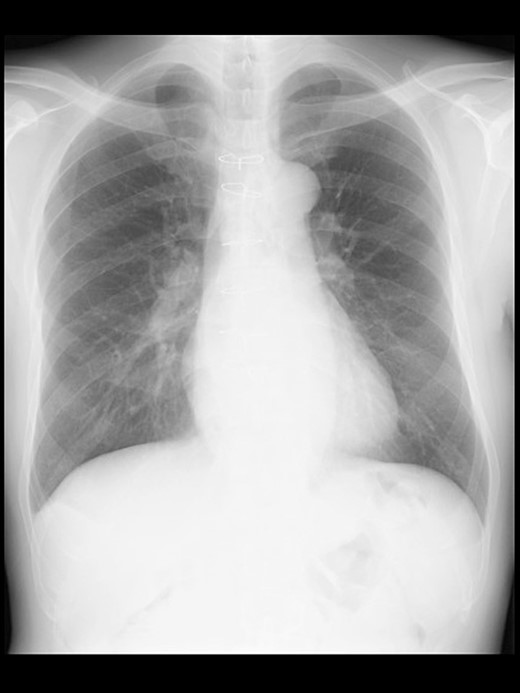

A 57-year-old male, 178 cm and 69 kg, was scheduled for a laparoscopic appendectomy for chronic appendicitis. The patient had undergone mitral valve repair for infective endocarditis via a median sternotomy 16 years before and minimally invasive esophagectomy (MIE) with intrathoracic anastomosis using a gastric tube for esophageal cancer 5 years before. Preoperative tests, including a chest radiograph (Fig. 1), were unremarkable. The computed tomography (CT) revealed no emphysematous lung cyst. Anesthesia was induced with intravenous remifentanil (0.3 μg/kg/min) and propofol (100 mg). Intravenous rocuronium (50 mg) was administered to facilitate tracheal intubation. Anesthesia was maintained with inhaled sevoflurane (1.5%) and intravenous remifentanil (0.1–0.3 μg/kg/min). The lungs were ventilated with a volume-guarantee pressure-controlled mode employing an inspired oxygen concentration of 35%. Percutaneous arterial oxygen saturation (SpO2) was maintained at 96%–100%. In addition to local anesthetic wound infiltration, intravenous fentanyl (300 μg) and acetaminophen (1000 mg) were administered for immediate postoperative analgesia. Operation and anesthesia times were 121 and 156 min, respectively. The infusion volume was 1350 ml. Emergences from anesthesia and extubation were uneventful. SpO2 in the postanesthesia care unit was maintained above 95% without supplemental oxygen. The patient did not complain of chest pain or dyspnea.